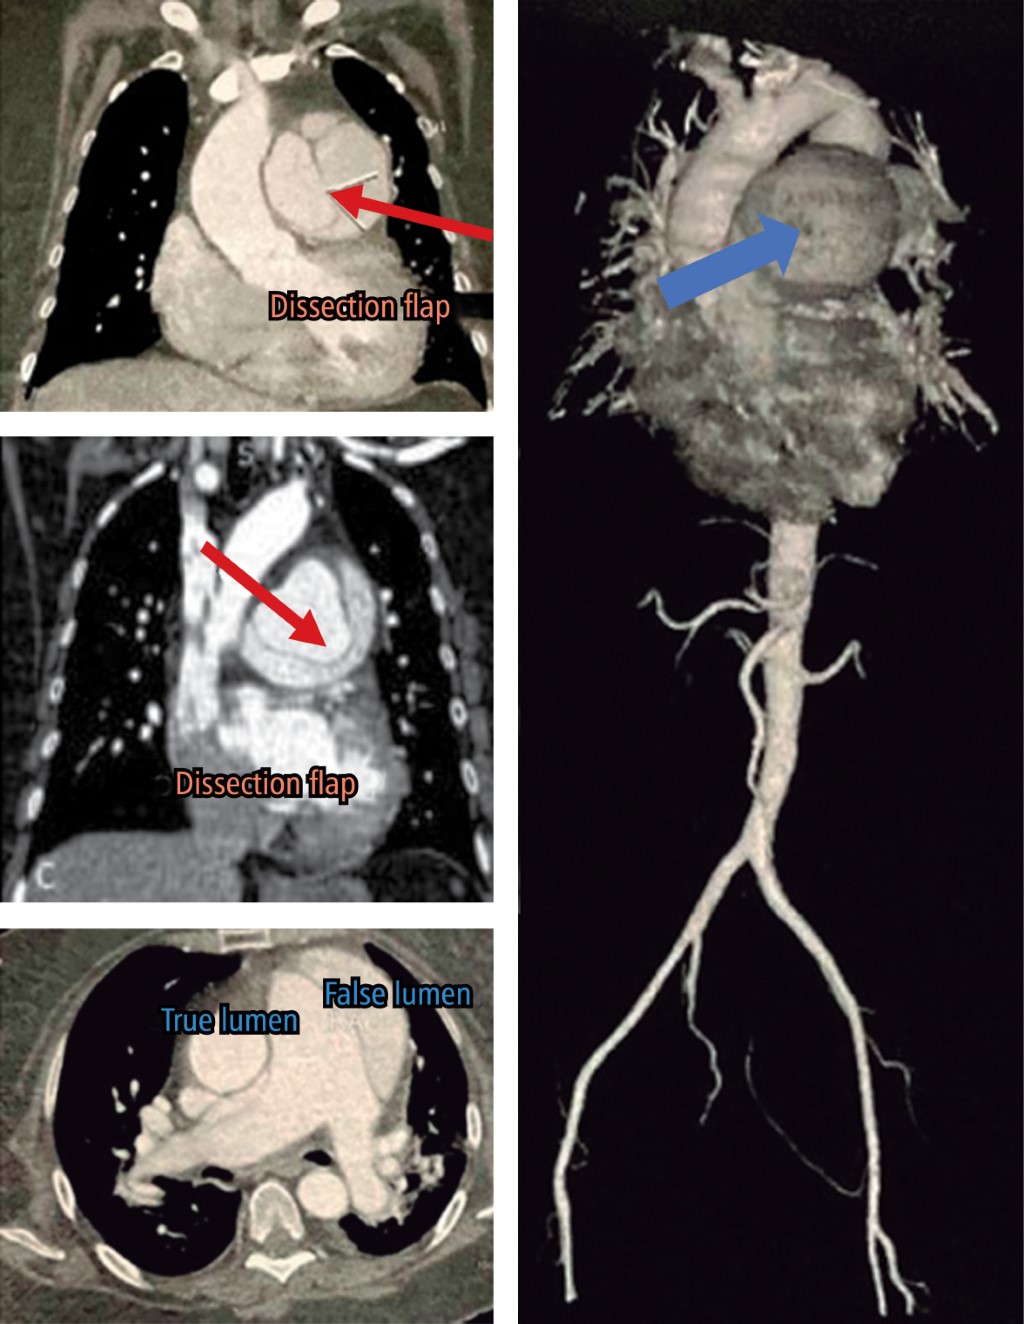

Objetivo: Describir la presentación de una disección de arteria pulmonar a la Unidad de Urgencias, la secuencia de eventos y revisión de la literatura. Reporte de caso: Paciente femenino de 59 años con cardiopatía chagásica conocida, quien acudió a urgencias por un episodio de dolor torácico repentino punzante y disnea progresiva, que evolucionó rápidamente a choque cardiogénico. Una radiografía de tórax informó un ensanchamiento severo del mediastino y cardiomegalia; por tanto, se realizó una angiotomografía torácica para descartar síndrome aórtico agudo, en la que se diagnosticó un aneurisma disecante de arteria pulmonar. El ecocardiograma transtorácico mostró un colgajo de la íntima a nivel de la arteria pulmonar y una dilatación severa. La paciente falleció en menos de 4 horas desde su llegada a urgencias sin poder acceder a tratamiento quirúrgico debido a la rápida evolución. Conclusión: La disección de la arteria pulmonar es una enfermedad rara, con una alta tasa de mortalidad. El manejo óptimo requiere un diagnóstico rápido con múltiples técnicas de imagen. Falta información sobre este tema.

Figura 1